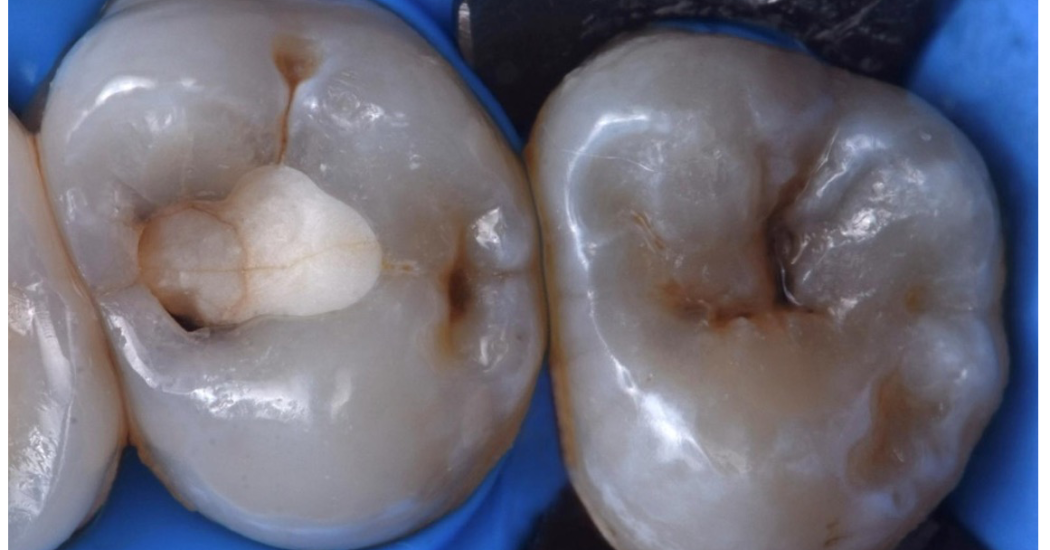

En este caso clínico, el Dr. Tosco (Italia) explica cómo aprovecha las propiedades terapéuticas y restauradoras de Biodentine™ XP para tratar dos dientes afectados por lesiones cariosas profundas, con el objetivo principal de conservar la vitalidad pulpar y mantener la integridad estructural de las piezas dentales.

Mantener la vitalidad pulpar es un objetivo fundamental en odontología restauradora, especialmente en pacientes jóvenes donde las lesiones de caries profundas pueden avanzar rápidamente. En estos casos, el recubrimiento pulpar indirecto representa un enfoque valioso para preservar la pulpa y evitar un mayor compromiso estructural. ”